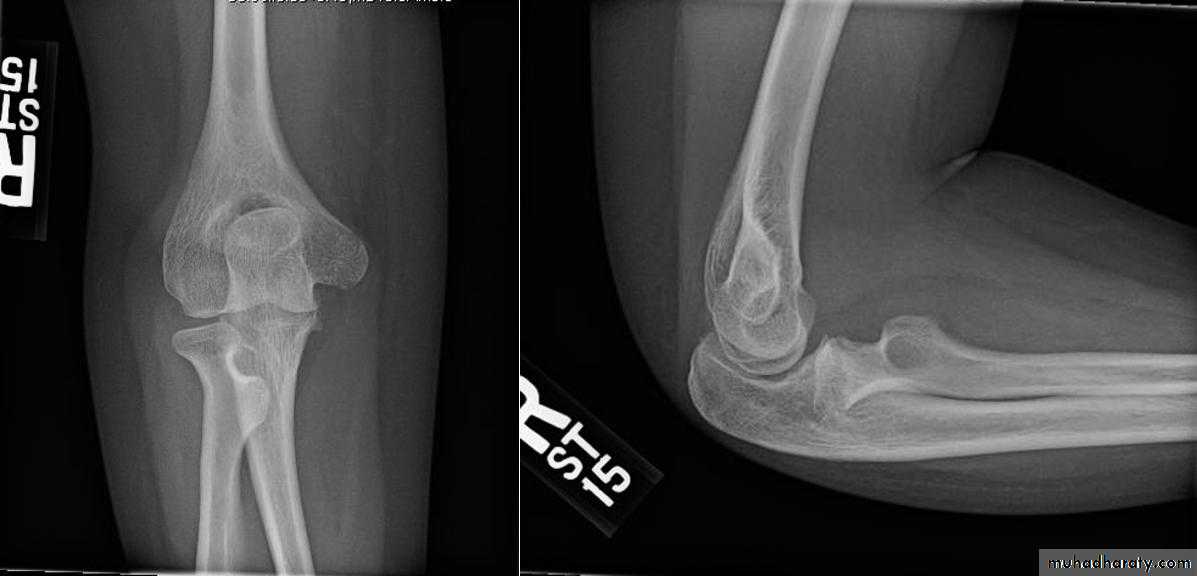

Cubitus varus

Malunion of supracondylar #Rx : wedge osteotomy of humerus